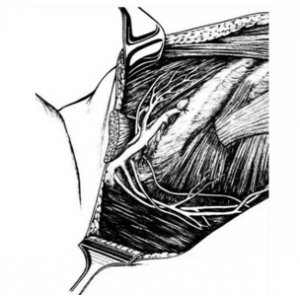

לאחר מכן כורתים את שריר החזה הגדול והקטן (Minor and major pectoralis). פותחים את בית השחי וכורתים את בלוטות הלימפה בשלושת האזורים של בית השחי (איור 24.12).

הגבולות האנטומיים של בית השחי, לצורך ניתוח זה, הם: מאחור - שריר הגב הרחיב (Latissimus dorsi) והשריר התת-שכמי (Subscapularis); מדיאלית - שריר המשור הקדמי (Serratus anterior) וצלעות בית החזה; מלפנים - שרירי הפקטורליס; ומעל - הווריד האקסילרי ממקום כניסתו לזרוע ועד האפקס של האקסילה שהוא אזור המעבר של הווריד האקסילרי מעל צלע 1 ומתחת לעצם הבריח. כל הבלוטות הנמצאות בתחום זה, כולל כלי הדם היוצאים מהווריד האקסילרי, נכרתות. בסיום כריתה זו מכסים את אזור הדיסקציה בשני מתלי העור, שהוכנו בזמן כריתת רקמת השד, ונתפרים ראשונית (איור 25.16 ותמונה 38.12).